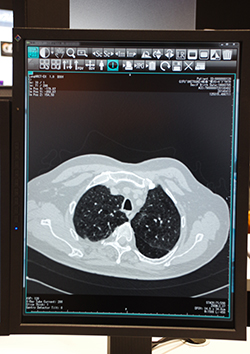

インフォコムは,RIS,PACS,読影ビューワレポートシステムなど,放射線部門のシステムを展示。各システムのシームレスな連携による放射線部門のソリューションを来場者に紹介していた。

RISの「iRad-RS」は,レポートシステム「iRad-RW」,検像システム「iRad-QA」,放射線治療システム「iRad-RT」などと同じサーバで運用するため,シームレスに各システムのデータを連携することが可能である。そのため,サーバに蓄積されたデータベースのデータを解析し,グラフ化するなど放射線部門の業務分析で,有用性を発揮する。iRad-QAとの連携では,同じ画面上で検像業務を行える。